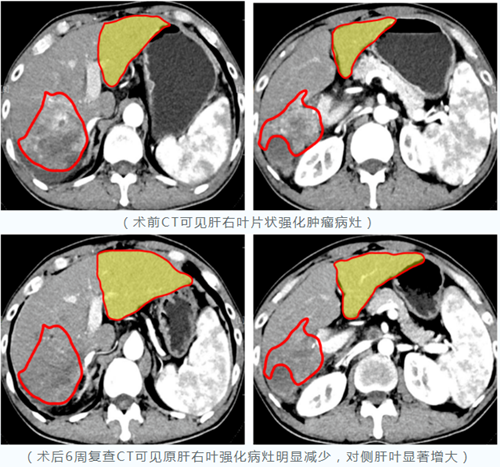

自2023年3月10日釔-90微球治療肝腫瘤項(xiàng)目落地西安國際醫(yī)學(xué)中心醫(yī)院以來,已有數(shù)十例肝癌患者經(jīng)篩選、評估并成功接受治療。術(shù)后復(fù)查結(jié)果顯示:釔-90“殺瘤”效果顯著,大肝癌或巨塊型肝癌經(jīng)治療后病灶明顯縮小,部分患者殘肝體積明顯增大;……